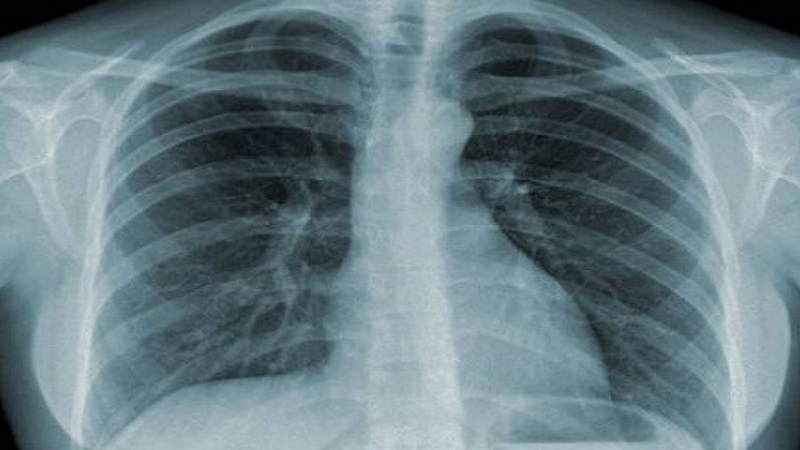

Nếu những cơn đau xuất hiện do hoạt động sai tư thế thì sau khi nghỉ ngơi, bạn sẽ thấy cơn đau thuyên giảm dần. Tuy nhiên, nếu như cơn đau kéo dài và dữ dội thì có khả năng bạn đã mắc phải những bệnh lý nguy hiểm như thoát vị đĩa đệm, thoái hóa cột sống, viêm khớp, gai cột sống… Nếu bạn vừa đau khớp lưng trên, vừa bị khó thở thì có thể bạn đã bị viêm phổi, lao phổi, nhồi máu cơ tim…

Phương pháp chụp X-quangPhương pháp chụp X-quang giúp cho bác sĩ đánh giá được các vấn đề về xương khớp ở vùng lưng trên và mức độ tổn thương của bệnh lý. Nếu những nguyên nhân gây đau khớp lưng trên do xuất phát từ phần mềm thì việc chụp X-quang sẽ không thể chẩn đoán được.